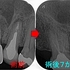

遠心縁下のカリエス処置

患者さんは50代男性

近医の先生からの紹介

親知らずの影響で第2大臼歯遠心にカリエスが出来てしまったということです。

幸い症状などはありません。

レントゲン

2026 EEdental MIH (1).jpg

かなり大きな虫歯があります。

患者さんにまず口腔外科で抜歯をしてもらい

術後3週間後に一度神経を残す方向でレジン充填を行い

痛みなどが出てしまったら、後で神経を取る処置を行なうと説明

患者さんにOKをもらい

2026 EEdental MIH (2).jpg

特殊な削り方をしてレジン(プラスチック)を詰めました。

親知らずの影響か、セメント質の肥厚が見られました。